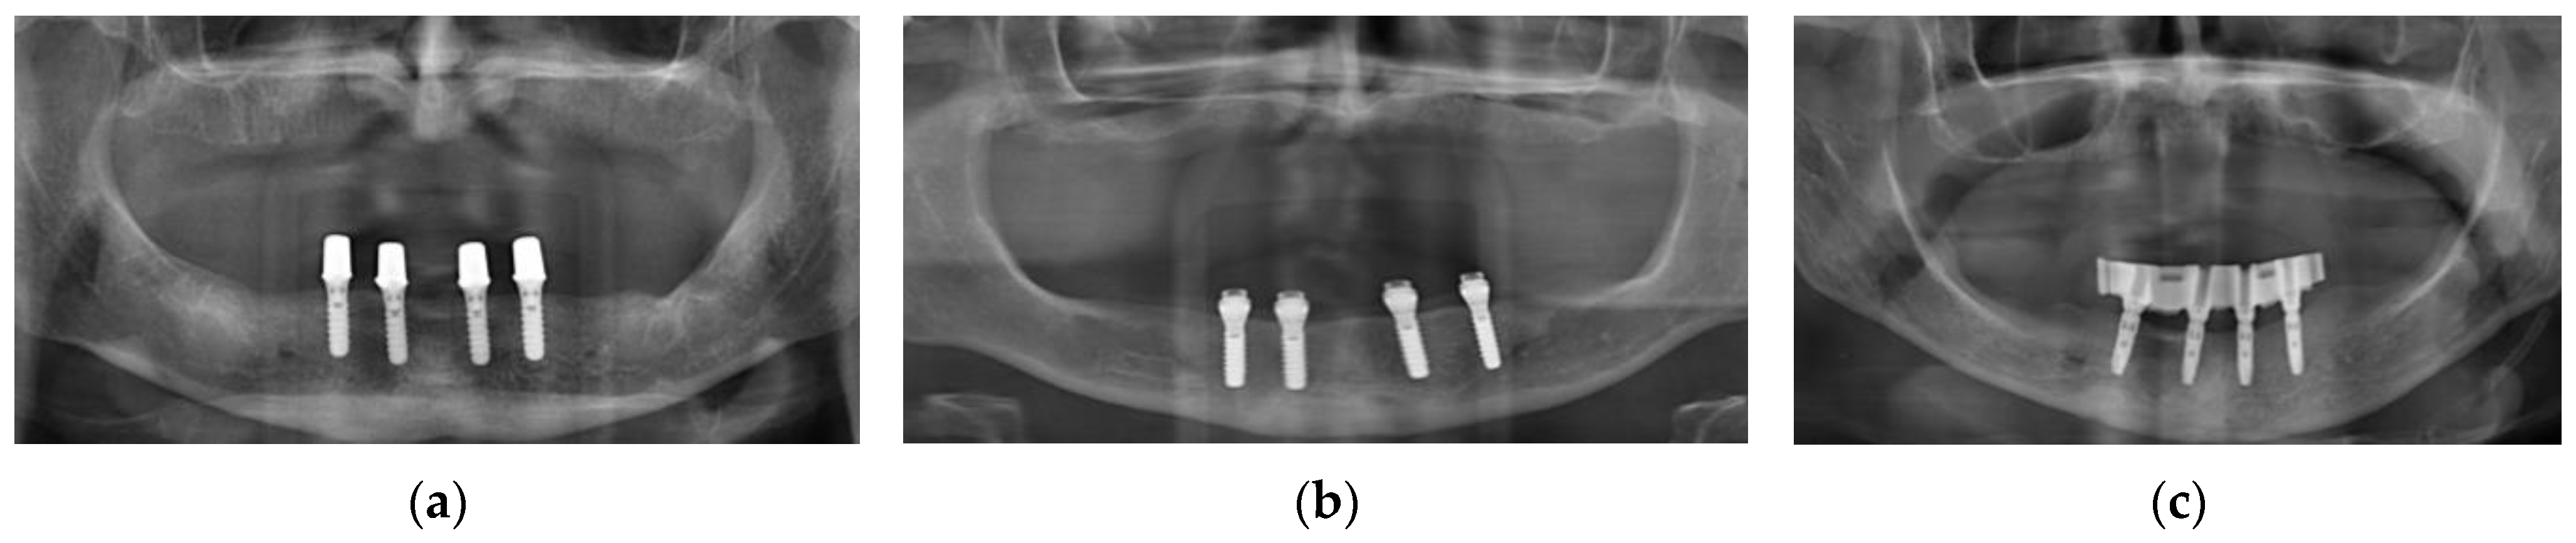

3.1. Retrospective Analysis of Complications